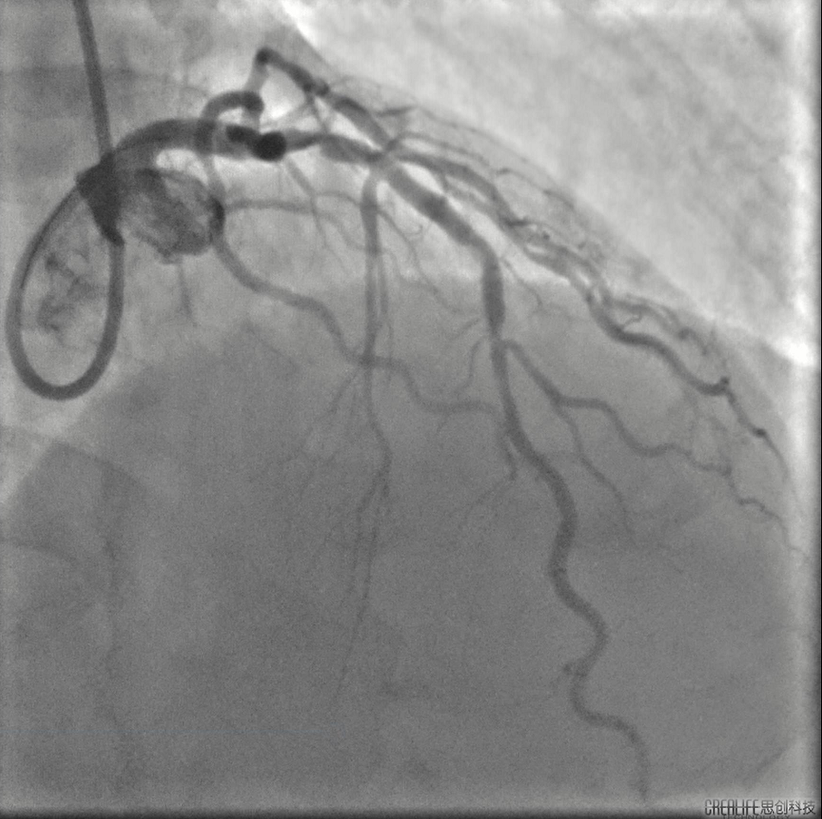

患者男,64岁,2022年6月5日急性下壁心肌梗死行介入干预,于右冠植入支架一枚,6月15日对左冠病变进行治疗。冠脉系统呈右侧优势型,右冠中段支架通畅。左主干大致正常,前降支近端至中段重度狭窄伴明显钙化。对前降支进行介入干预,以2.5*15mm球囊预扩张后,在前降支中段植入2.5*18mm Resolute支架,之后尝试在前降支近端植入 3.0*26mm支架不成功,经反复预扩张后,支架仍无法通过病变,血管内超声证实前降支近端可见环形钙化并重度狭窄。

庄晓东教授:该患者前次介入时未进行充分病变预处理即植入支架,造成支架膨胀不全,支架近端和远端仍残留钙化狭窄病变。尝试在近端病变植入支架不成功,即使使用切割球囊反复扩张,支架仍无法通过。旋磨可能需要通过支架对支架远端病变及近端病变进行处理,容易出现磨头嵌顿等并发症,冠脉内冲击波球囊钙化斑块碎裂术能有效打断环形钙化,对支架又不会造成额外破坏,且Shockwave球囊操作便捷,安全性好,是该病人目前治疗的最优策略。

胡洵教授:术前Oct可见前降支中远段严重钙化病变,部分节段呈360度钙化环,最大钙化厚度0.8 mm,中段原支架最小支架面积3.9mm2,支架膨胀率63%,支架外可见明显钙化斑块,近段已用3.0shockwave冲击波球囊进行30次脉冲冲击,钙化病变处可见多处断裂,最深断裂处可达 0.55mm,使用3.0shockwave球囊于中段原支架膨胀不良处进行50次脉冲冲击,2.5shockwave球囊于中远段钙化病变处进行30次脉冲冲击,再次复查Oct可见中远段钙化环出现多处断裂,中段原支架膨胀不良处支架面积明显改善,在前降支远段植入2.5支架,中段原支架内予以3.0高压球囊扩张,近段植入3.5支架并用3.5高压球囊扩张,最后复查Oct见远段支架最小面积 4.21mm2,支架膨胀率75%,中段原支架最小支架面积5.08mm2,支架膨胀率75%,近段最小支架面积 10.20mm2,支架膨胀率85%。